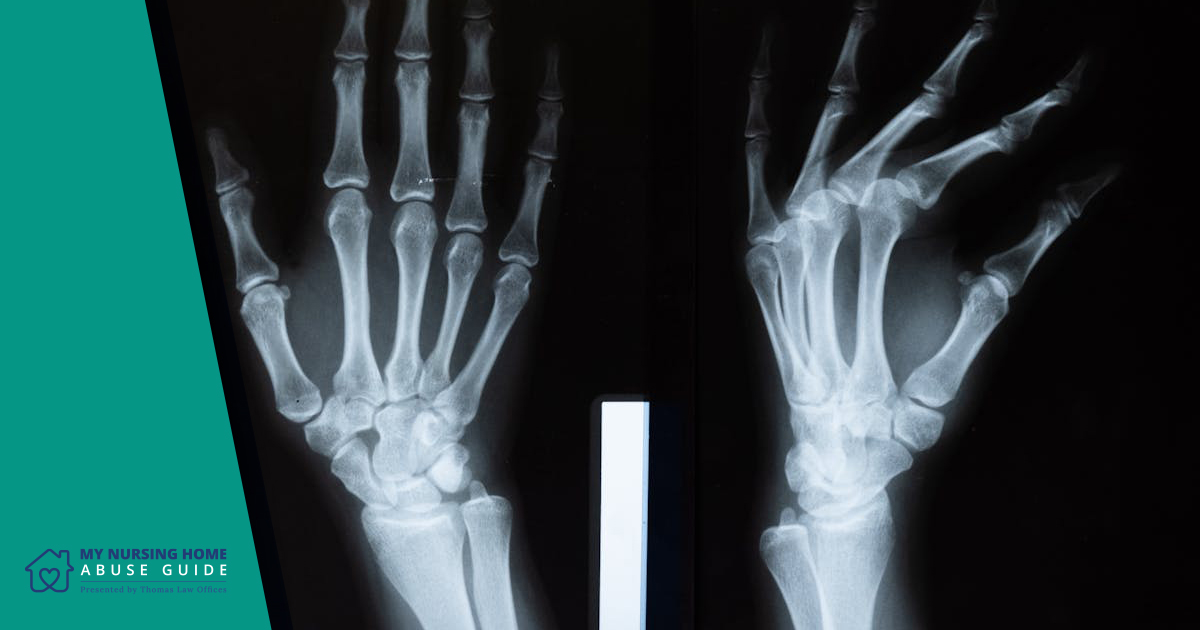

Being restrained can also put strain on muscles and joints. Residents who struggle against restraints may experience sprains, dislocations, or even broken bones.

Older adults are especially vulnerable to these injuries because their bones are often more fragile, and their muscle strength is reduced. Over time, forced immobility can also lead to muscle wasting and decreased range of motion, making it harder for residents to walk or perform daily tasks.

These injuries not only cause pain but also reduce independence and quality of life.